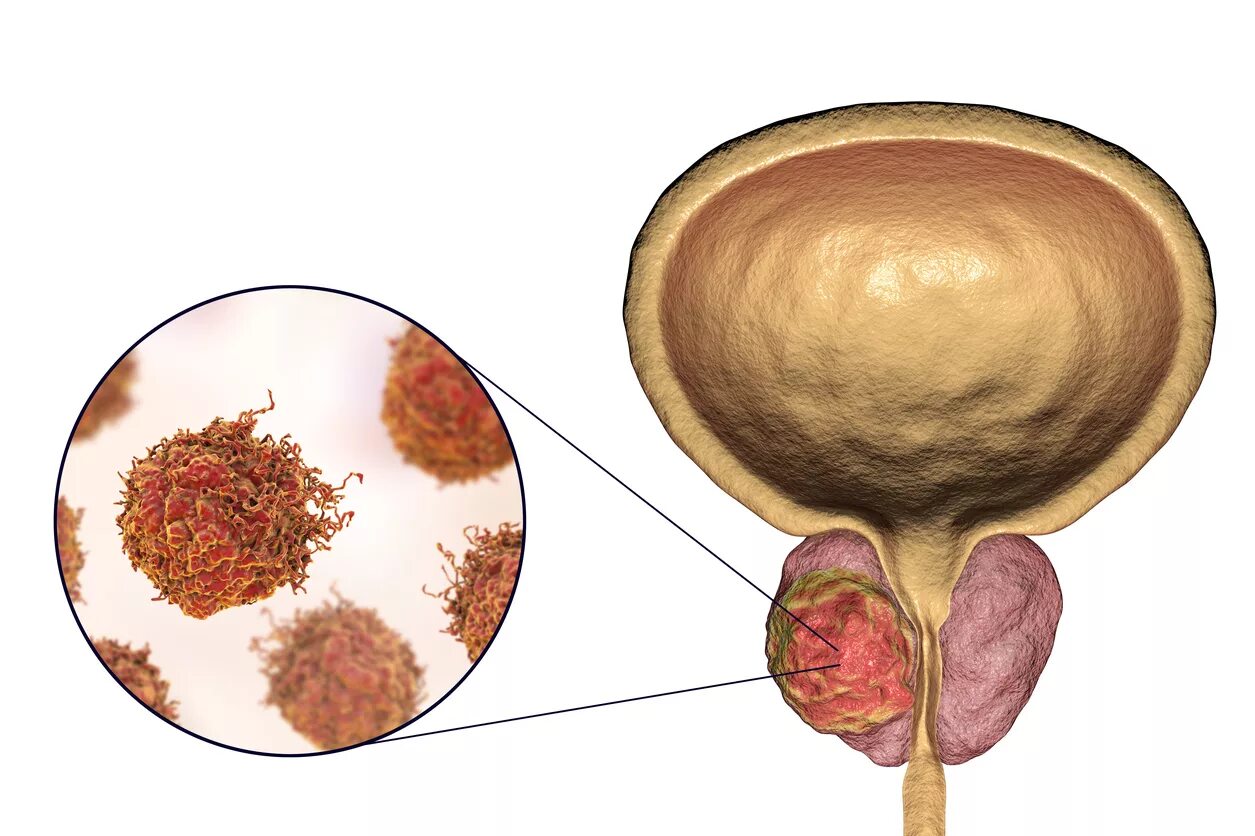

Опухоль простаты

Опухоль аденомы простаты симптомы. Раковые заболевания простаты. Раковая опухоль простаты. Предстательная железа у мужчин онкология

Опухоль аденомы простаты симптомы. Раковые заболевания простаты. Раковая опухоль простаты. Предстательная железа у мужчин онкология Злокачественная опухоль простаты. Злокачественное новообразование предстательной железы. Злокачественные новообразования простаты

Злокачественная опухоль простаты. Злокачественное новообразование предстательной железы. Злокачественные новообразования простаты Карцинома предстательной железы. Злокачественное новообразование предстательной железы. Cancer предстательной железы. Аденома предстательной железы – это опухоль

Карцинома предстательной железы. Злокачественное новообразование предстательной железы. Cancer предстательной железы. Аденома предстательной железы – это опухоль Предстательная железа, Prostata. Аденома предстательной железы. Карцинома предстательной железы. Злокачественное новообразование предстательной железы

Предстательная железа, Prostata. Аденома предстательной железы. Карцинома предстательной железы. Злокачественное новообразование предстательной железы Cancer предстательной железы. Аденокарцинома предстательной железы. Онкология предстательной железы

Cancer предстательной железы. Аденокарцинома предстательной железы. Онкология предстательной железы Опухоль предстательной железы у мужчин. Злокачественное новообразование предстательной железы. Эктопия предстательной железы. Карцинома предстательной железы

Опухоль предстательной железы у мужчин. Злокачественное новообразование предстательной железы. Эктопия предстательной железы. Карцинома предстательной железы